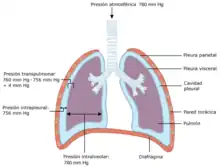

- Pleura y cavidad pleural: La pleura es una membrana serosa que recubre ambos pulmones. Consta de dos capas, la pleura parietal en contacto con la pared del tórax y la pleura visceral en contacto con los pulmones. Entre ambas capas queda un espacio que se llama cavidad pleural. La presión en la cavidad pleural es menor que la presión atmosférica lo cual hace posible la expansión de los pulmones durante la inspiración.

Presiones en el aparato respiratorio

Deben considerarse cuatro presiones diferentes para comprender el funcionamiento del aparato respiratorio humano. Estas presiones no son constantes, pues se modifican a lo largo del ciclo respiratorio.

- Presión atmosférica. Corresponde a la presión del aire en la atmósfera.

- Presión alveolar o intrapulmonar. Es la presión del aire contenido en los alvéolos.

- Presión pleural o intrapleural. Es la presión existente en la cavidad pleural, es decir en el espacio situado entre la pleura visceral y la pleura parietal. La presión pleural es negativa y por lo tanto menor que la atmosférica.

- Presión transpulmonar. Corresponde a la diferencia entre la presión alveolar y la presión pleural.